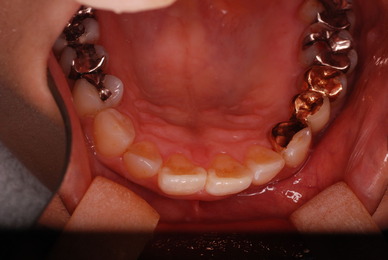

神経が死んでしまった歯は脆いのです。

重症の歯周病で削って上の歯とぶつからないようにしていた歯ですが

いつの間にか神経が死に歯の中が腐っていたようです。

それでヒビが入り割れてしまいました。